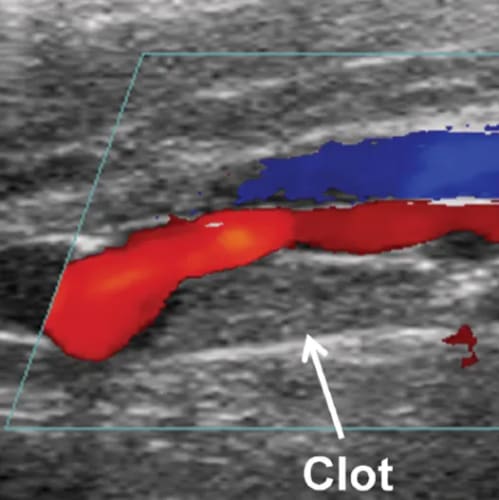

Vascular Services

Allow our dedicated team to put you at ease, while we boast about having top of the range equipment and overqualified staff. Outstanding patient care comes as standard here at NumiScan Basingstoke.